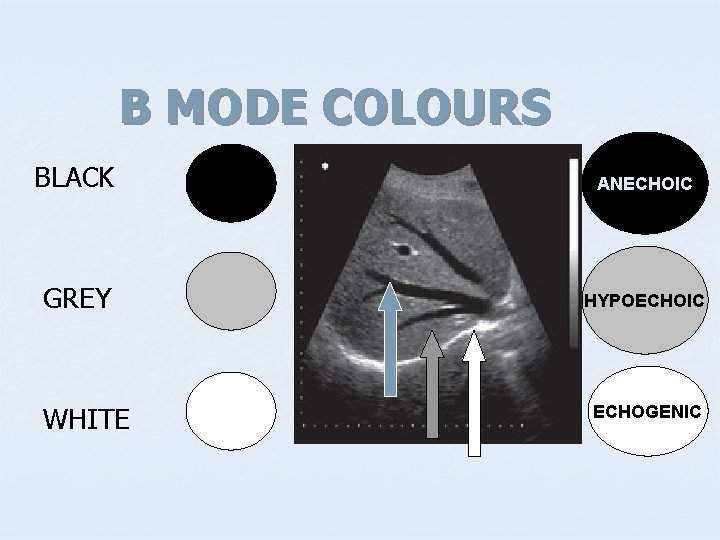

B MODE COLOURS BLACK ANECHOIC GREY HYPOECHOIC WHITE ECHOGENIC

APPEARANCE OF DIFFERENT TISSUES STRUCTURE APPEARANCE Viscera ; Liver Spleen Hypoechoic Muscles Hypoechoic with echogenic lines Blood, Urine, Bile, ascites, water Anechoic Bone, Stone Hyperechoic